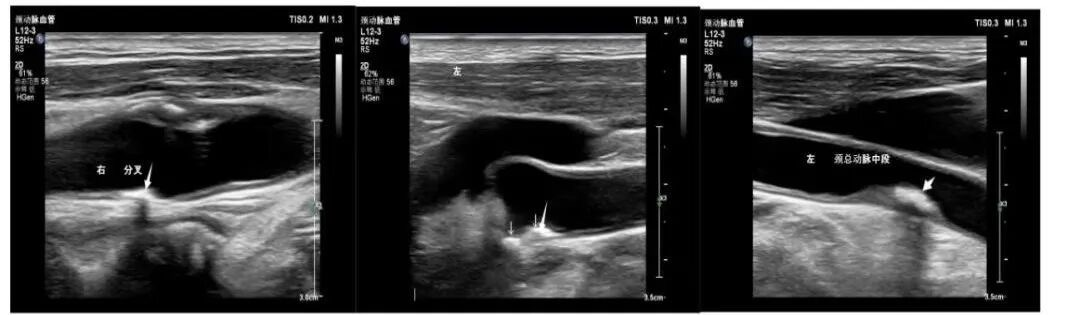

在颈动脉超声检查中,不少人发现自己的检查报告中有“强回声斑块”“低回声斑块”“混合回声斑块”,颈动脉斑块形成,让人很容易焦虑,会想到是否和脑梗有关?需不需要吃药或者手术治疗?究竟哪些斑块是有风险的?

颈动脉使用彩色超声检查,报告单上的各种“回声”代表着斑块的内容物与质地。

硬斑块——等回声与强回声代表超声波遇到了较硬的物质,所以反射回声较多。表示斑块内可能含有较多纤维组织,或有钙化,为稳定斑块,也称为“硬斑块”。

软斑块——无回声与低回声、混合回声代表超声波被吸收,所以反射较少,表示斑块内可能有出血、炎症或是有较大的脂质内核,为不稳定斑块,也称为“软斑块”。如果出现“混合回声”则代表回声区域情况复杂,可能是坏死细胞形成的钙化、出血、炎症渗出、较大脂质核心等混杂在一起,为不稳定斑块,是危险性较大的软斑块。